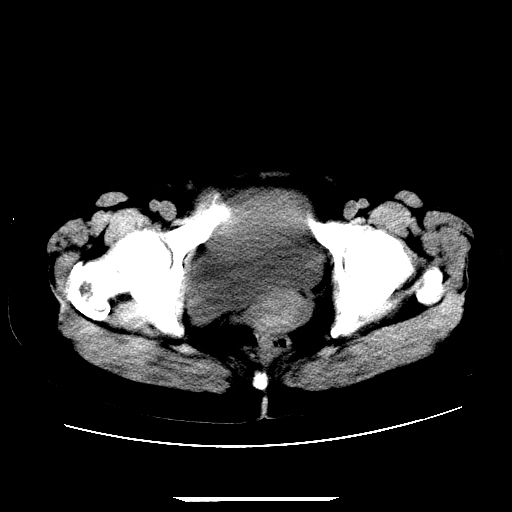

f,45y.怀孕4月晕倒,b超提示死胎,有手术结果,请展开讨论后明天告诉。

膈下-肠间隙内见气体密度影,子宫轮廓显示不清,宫腔-腹腔积液,首选考虑---子宫破裂出血。

1)宫腔妊娠。2)子宫破裂出血,腹腔及盆腔积血。

感谢同行们的高见。手术结果:子宫破裂出血。

我们的诊断是:腹、盆腔积液(考虑腹盆腔脏器破裂出血);宫腔妊娠。让人纳闷的是当时我们没有经验,现在回头看看分析:4月宫腔妊娠:1、洋膜囊不可能紧贴胎体这么小;2仔细看看子宫后壁肌层模糊不清;3腹、盆腔液体来源原因?4、45岁高龄妊娠有晕倒。由此可大胆诊断:宫腔妊娠子宫破裂出血。